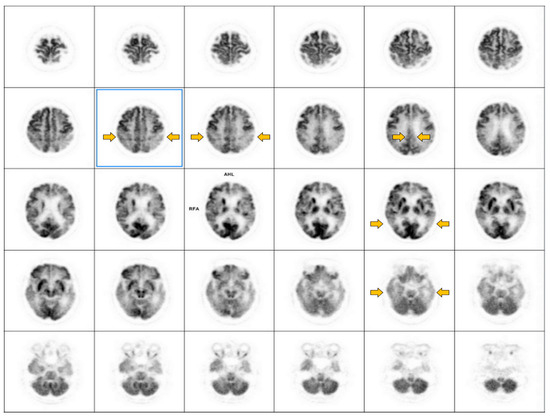

6.3. Tau PET

6.3.1. Imaging Data Display

6.3.2. Image Interpretation for Tau PET

Visual Analysis

Quantitative Analysis

6.3.3. Reporting Format

- -

- History: Indication, the patient’s clinical presentation, and correlative imaging.

- Techniques: Imaging is performed on an integrated 64-slice PET/CT scanner for the whole brain, with non contrast-enhanced CT for attenuation correction and localization in the transaxial, coronal, and sagittal planes. A 3D emission dynamic scan of the same area is acquired in a one-bed positionSemiquantitative calculations are performed using PMOD software with the automatic anatomical labeling (AAL)-merged atlas to generate automatic voxels of interest for different brain regions.

- Findings: Visual analysis: Describe abnormal tau deposition in the brain region.

- Interpretations/Impressions/Conclusions: Negative/positive studies should be mentioned when reporting the region of abnormal tau deposition.